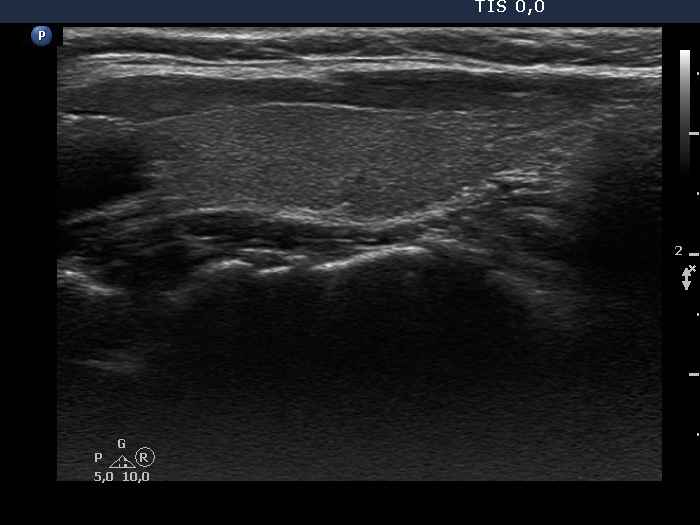

Consecutive patients with the final diagnosis of Hashimoto's thyroiditis - case 40 (1322) (ultrasonographic picture 5)

Left lobe, longitudinal view.